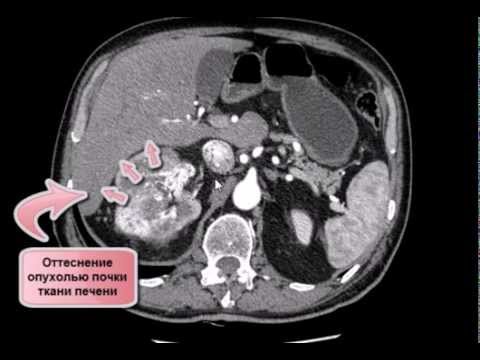

КТ брюшной полости (опухоль почки и тромбоз полой вены)